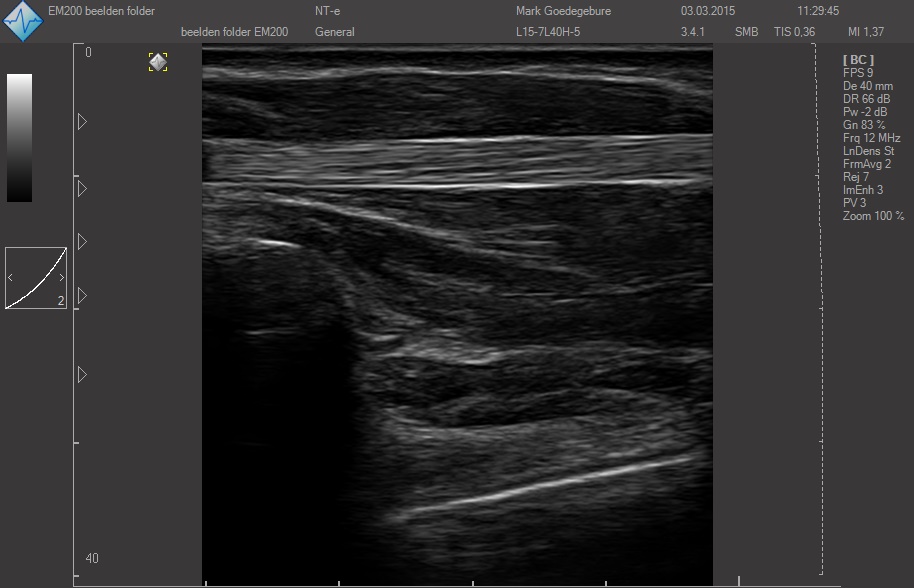

ЗДЕСЬ Вы можете посмотреть реальные кинопетли с аппарата УЗИ SmartUs.